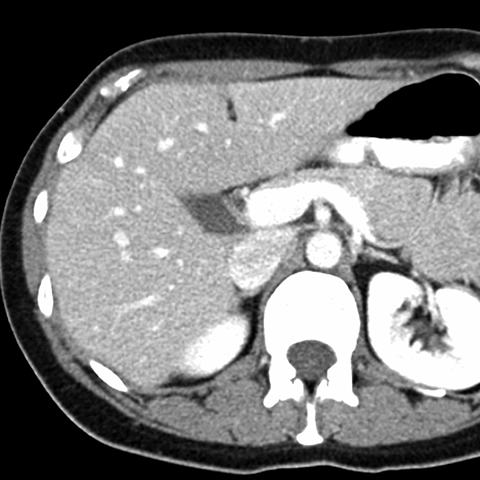

Normal Liver, CT ( axial ) [7 of 9]